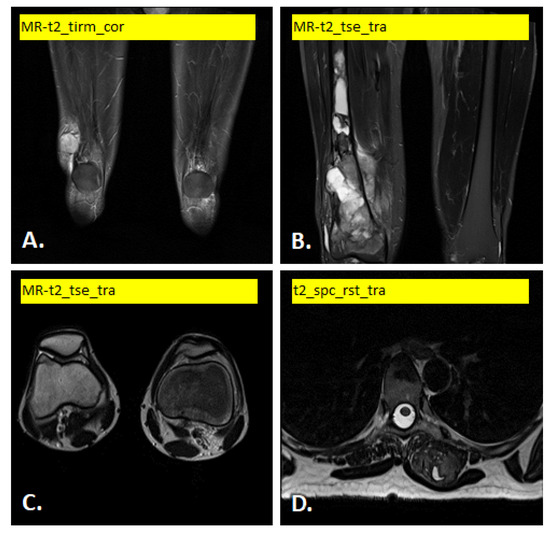

In Figure 1 and Figure 2 illustrate examples of the different images used.

Figure 2. Example of T2-weighted MRI scan variants: (A) soft tissue tumor in lower end of right vastus lateralis muscle, (B) bone tumor in lower end of right femur, (C) soft tissue tumor in synovia of right knee joint and (D) soft tissue tumor in left erector spine muscle.